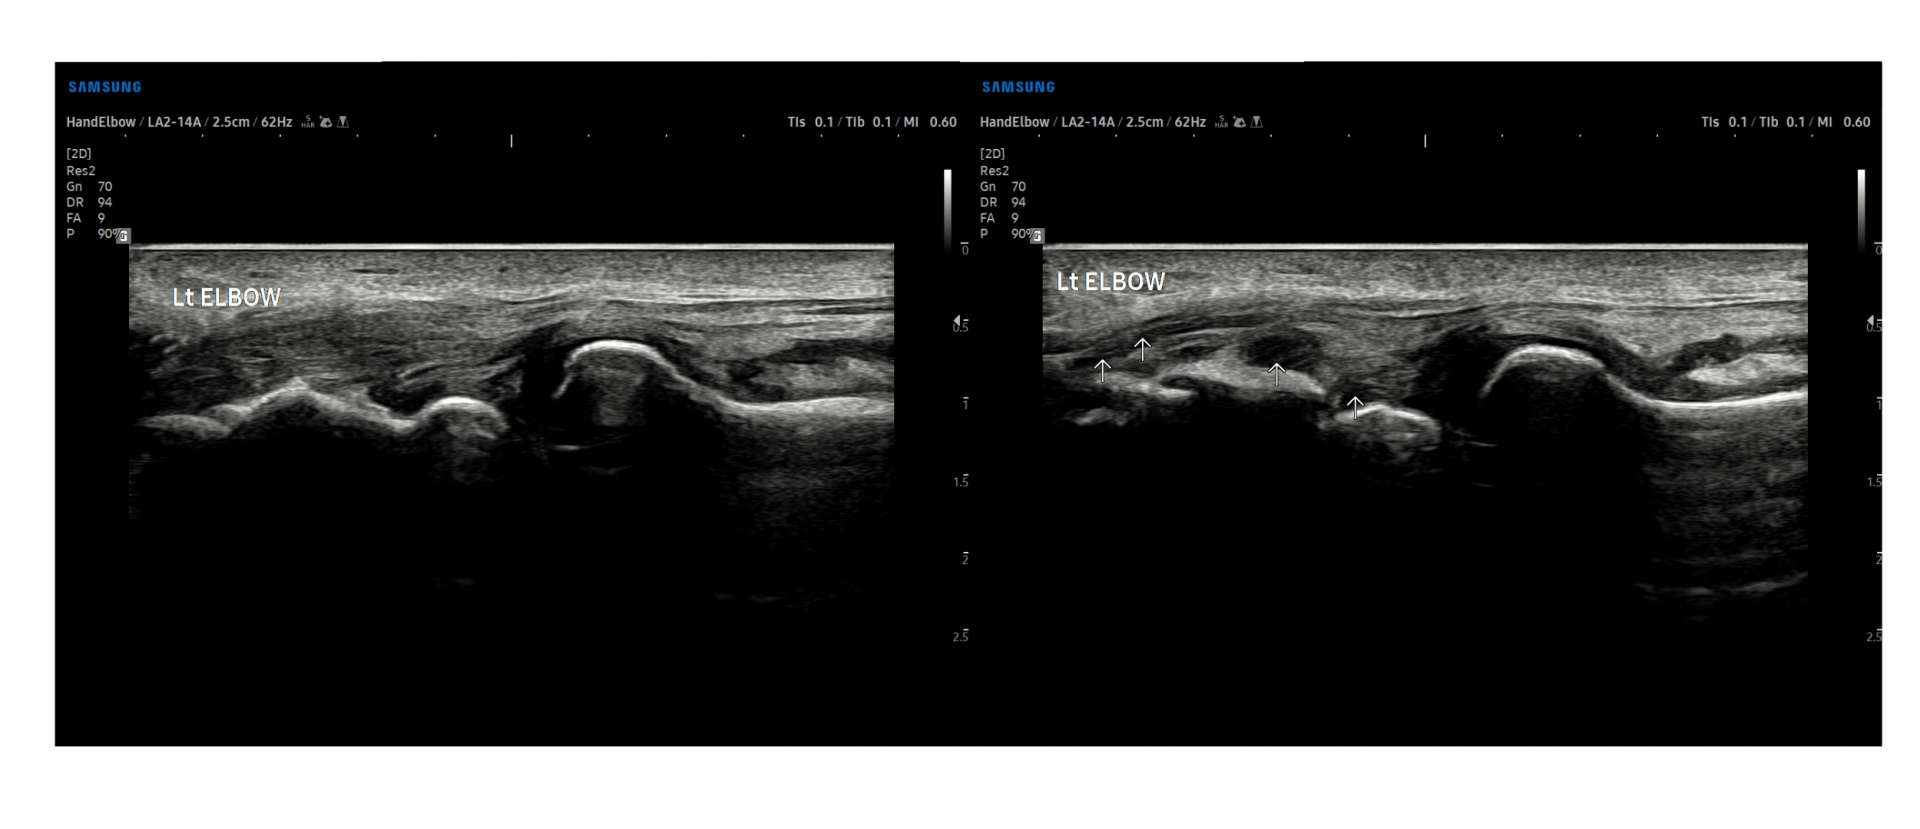

- 치료기간 : 25 . 5 . 7 ~ 25 . 8 .12

- 치료횟수 : 4cycle(20) 회

치료전

치료후